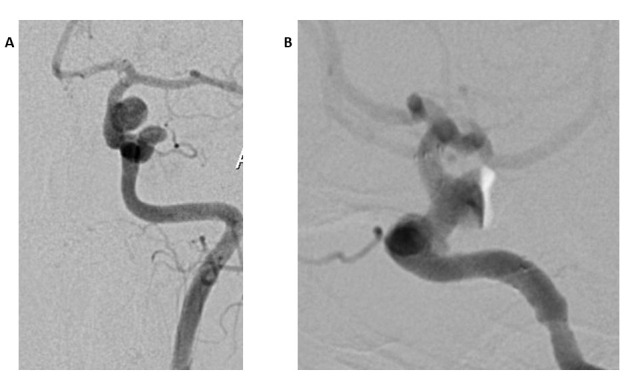

脑动脉瘤,也被称为脑动脉瘤,是母体动脉的生长。根据其形状,动脉瘤可分为囊状动脉瘤和非囊状动脉瘤。多种因素与多发性脑动脉瘤有关,但最常见的是动脉高血压。在脑动脉瘤的治疗中,像线圈栓塞这样的血管内技术基本上已经取代了手术夹闭。由于分流器的出现,脑动脉瘤的治疗发生了革命性的变化。它们现在用于治疗对标准治疗无反应的复杂动脉瘤,以及以前用标准手术或基于线圈的血管内手术治疗的未破裂病变。由于分流术并发症少,恢复率高,已被证明是一种比其他方法更成功的治疗动脉瘤的方法。我们讨论的情况下,病人谁到达头痛和随后被诊断为许多动脉瘤的左颈内动脉。血流分流支架植入用于栓塞患者现有的动脉瘤,随后作为术后需要进行双重抗血小板治疗(替格瑞洛和血栓ASS)。尽管我们的病人有大动脉瘤和小动脉瘤,但治疗后没有并发症。

Brain aneurysms, also known as cerebral aneurysms, are the growths of the parent artery. Based on their shape, aneurysms can be categorized as saccular or non-saccular. Several factors have been linked to multiple brain aneurysms but the most prevalent is arterial hypertension. In the treatment of cerebral aneurysms, endovascular techniques like coil embolization have essentially taken the place of surgical clipping. Brain aneurysm treatment has undergone a revolutionary change owing to flow diverters. They are now used for complex aneurysms that are unresponsive to standard therapies, in addition to unruptured lesions that were previously treated with standard surgical or coil-based endovascular procedures. Flow diversion has shown to be a more successful treatment for aneurysms than other approaches due to its reduced complication and high recovery rate. We discuss the case of a patient who arrived with headache and was subsequently diagnosed with numerous aneurysms of the left internal carotid artery. Flow diverter stenting was employed to thrombose our patient's existing aneurysms, followed by dual antiplatelet therapy (Ticagrelor and Thrombo ASS) as a post-procedural need. Despite the fact that our patient had both large and minor aneurysms impacting challenging locations, there were no complications after treatment.